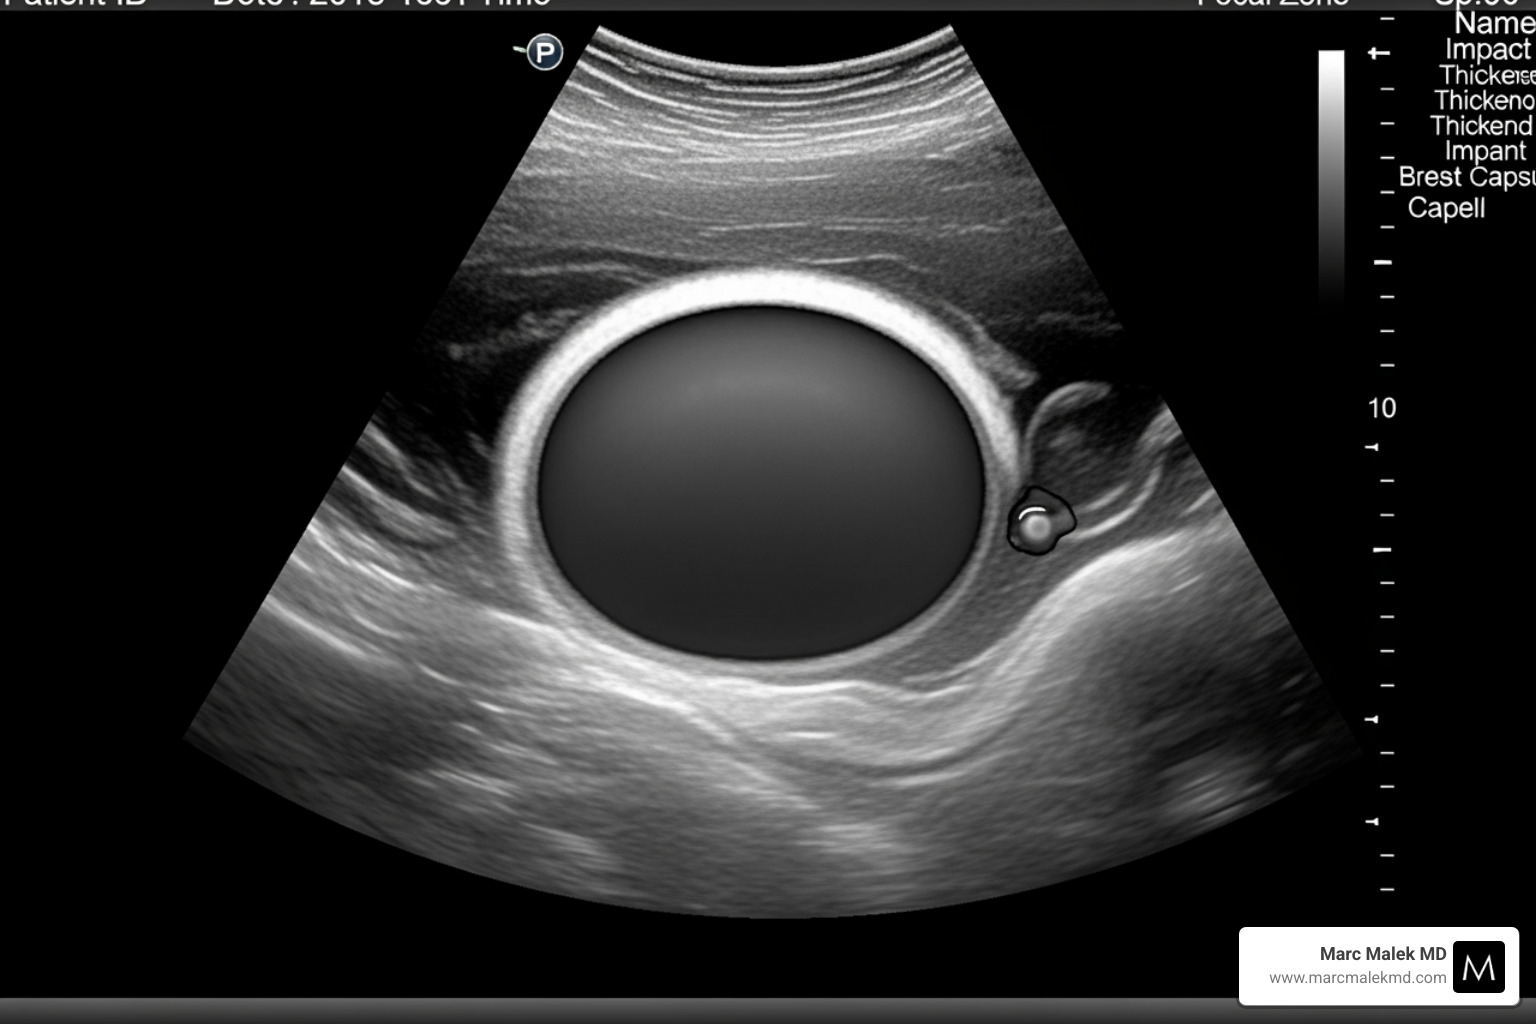

- Ultrasound: This non-invasive imaging technique can visualize the implant and the surrounding capsule. It helps us assess the thickness of the capsule and check for any irregularities or fluid collections. An ultrasound grading system, like the one proposed by Zuniga et al., can objectively measure capsule thickness and identify abnormal wrinkles or deformities.